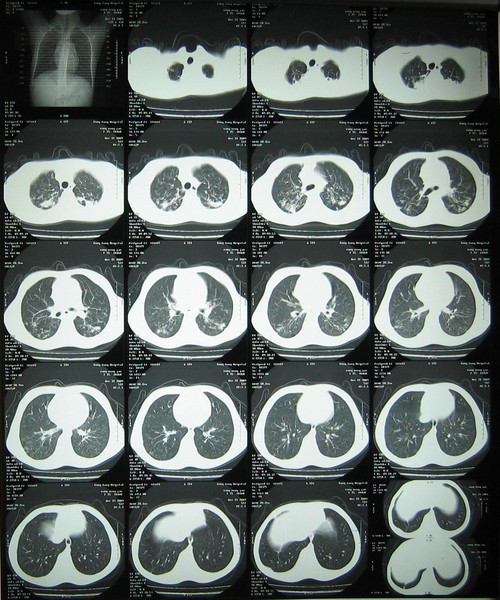

如何消除肺結(jié)核危害?

結(jié)核病仍然是全球各類傳染病的首位殺手,全球有1/3的人 (約20億)感染了結(jié)核病?,F(xiàn)有結(jié)核病人約2000萬。每年新增病人約900萬,每年死亡人數(shù)達(dá)到300萬人。消除結(jié)核病是一項共同任務(wù),需要所有人的努力。如何消除結(jié)核危害呢?